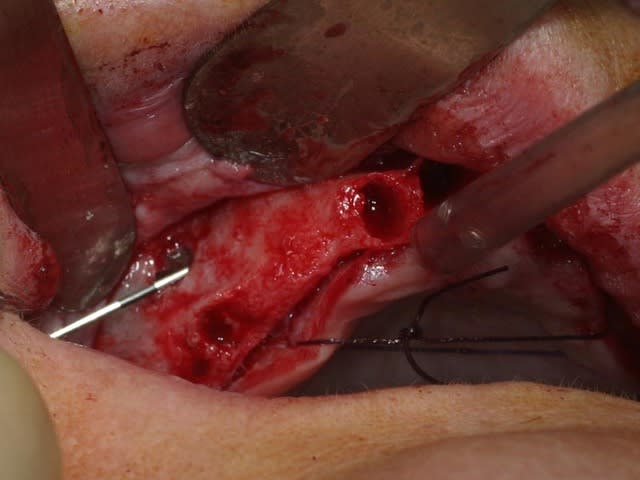

bon, toujours aussi speed je suis, mais après certaines réclamations, et malgrès ma réticence à poser un cas non "consolidé", voici en avant première mon premier all on 4, version photos ratées et non retouchées, mais... speed je suis je vous disais ;)

sto le bla bla, et pasons le diaporama... bon voyage au pays de la mise en charge immédiate totale au maxillaire de fille carole sur dame ginette, une patiente en or que j' adore, et pour qui je suis très très heureuse d' avoir pu réaliser cette chirurgie et la première étape prothétique.....

cependant, j'ai parfois ressenti le besoin de faire des petits tracés au crayon sur l'os: c'est quoi comme crayon? autoclavable? on le trouve où?

Tu as utilisé des Nobel Speedy si je ne me trompe pas.

Peux tu nous en dire un peu plus sur les implants, leurs diamétres et leur longueurs ?